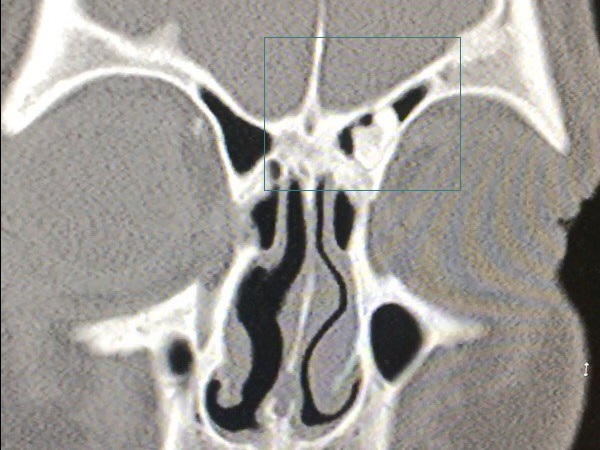

До нас звернувся пацієнт зі скаргами на утруднення носового дихання, періодичний головний біль. На КТ виявлено доброякісне новоутворення, щільну структуру, що росте з кісткової тканини (остеома).

Особливістю остеом є деструктивне зростання – руйнація навколишніх структур під час зростання.

При ендоскопічній ендоназальній фронтотомії зліва виявлено щільне новоутворення горбистій форми, що росте із задньої стінки лобової пазухи. Здійснено його мобілізацію та зменшення у розмірі за допомогою спеціального обладнання. Новоутворення видалено через лобоносову кишеню.

Зовнішній доступ використовується за неможливості ендоскопічного. Ендоскопічний доступ функціональний, менш травматичний, можливий за невеликих розмірів остеоми.